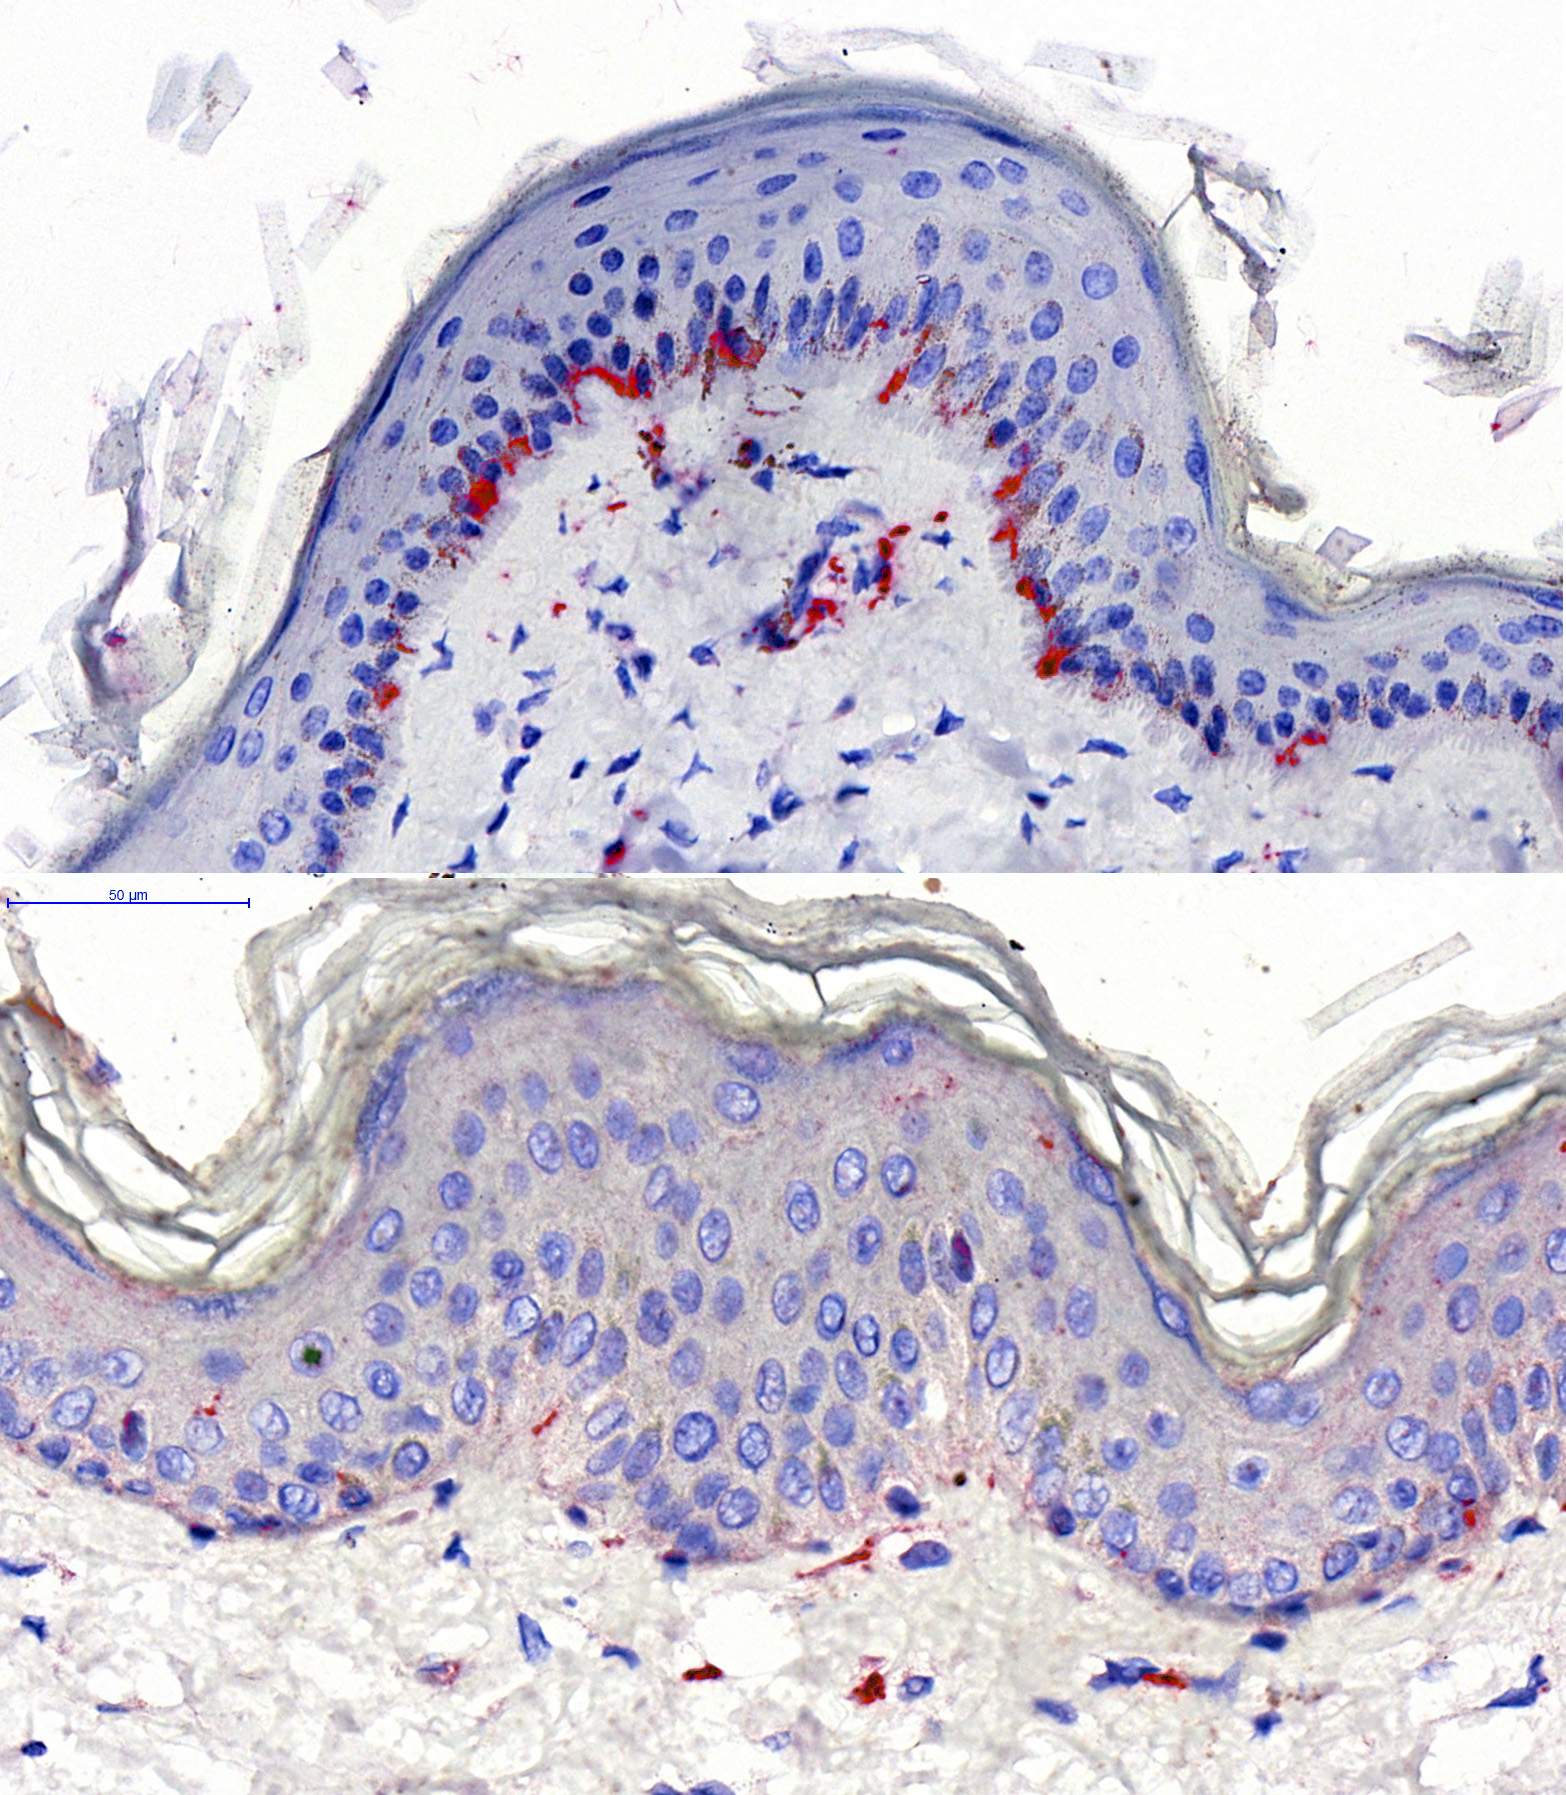

From www.researchgate.net

Histological cross section of skin from a horse of the study group at Horse Skin Vs Human Skin we decided to see if horse skin thickness and nerves were really that different to human. To do this, i took a piece of horse skin from the flank area (the area where. The darker layer shown here is the epidermis. The study, published in the journal animals and funded by rspca. when one forensic veterinary pathologist actually. Horse Skin Vs Human Skin.